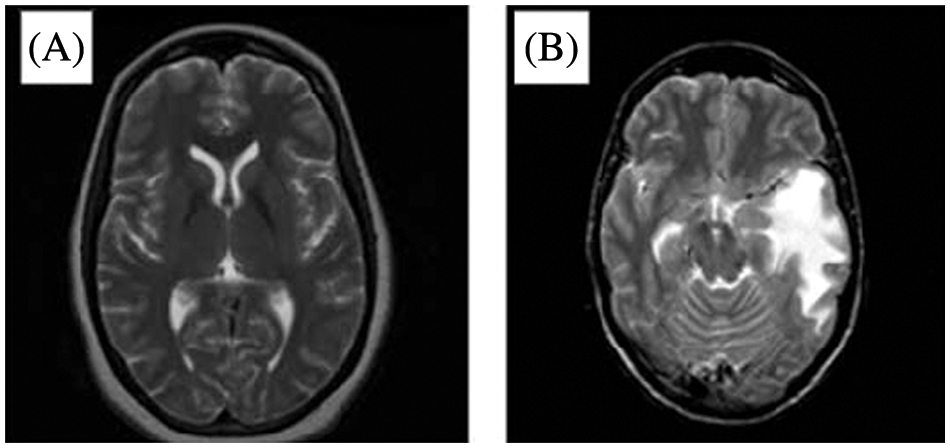

The analysis of tumors for their location, size, and shape is complex [1,2]. MRI scans can offer in-depth information about the soft tissues in the human body and provide an outline of a tumor if it exists [2,3–6]. That said, manual analysis of an MRI can lead to an inaccurate diagnosis of brain tumors [2]. Still, attempting these challenges is critical to patient care. The early diagnosis and detection of tumors can provide an excellent, timely treatment to elevate the survival ratio [2–4]. Compared to other parts of the human body, diagnosing a brain tumor is particularly difficult because the brain is filled with the Blood-Brain Barrier (BBB) [2]. MRIs are a preferred technology in brain tumor detection since they can capture disruptions in the BBB [2,5–9]. Around 227,000 deaths are reported annually due to brain tumors, and 7 to 11 out of 100,000 are diagnosed with brain tumors [2]. Three main components comprise the brain’s anatomy: the stem, cerebrum, and cerebellum [3]. The World Health Organization (WHO) classifies brain tumors among four types, known as grades. These four grades indicate whether a cancer is slow-growing or aggressive [3,10–13]. The first grade refers to tumors that grow slowly and do not spread excessively [3]. The second grade represents tumors that grow slowly and can spread to other tissues [3]. Second-grade tumors can come back after surgery. The third grade denotes tumors that grow faster than the previous two grades and spread to neighboring tissues [3–6]. These tumors are treated by surgery and post-surgical treatment such as radiotherapy or chemotherapy [3]. The fourth grade refers to the most destructive and spreadable tumors [3]. Fig. 1 illustrates a healthy brain on the left-hand side and a brain with a tumor on the right-hand side of an MRI image as in [14].

Figure 1: MRI of (A) A healthy brain and (B) A brain with a tumor